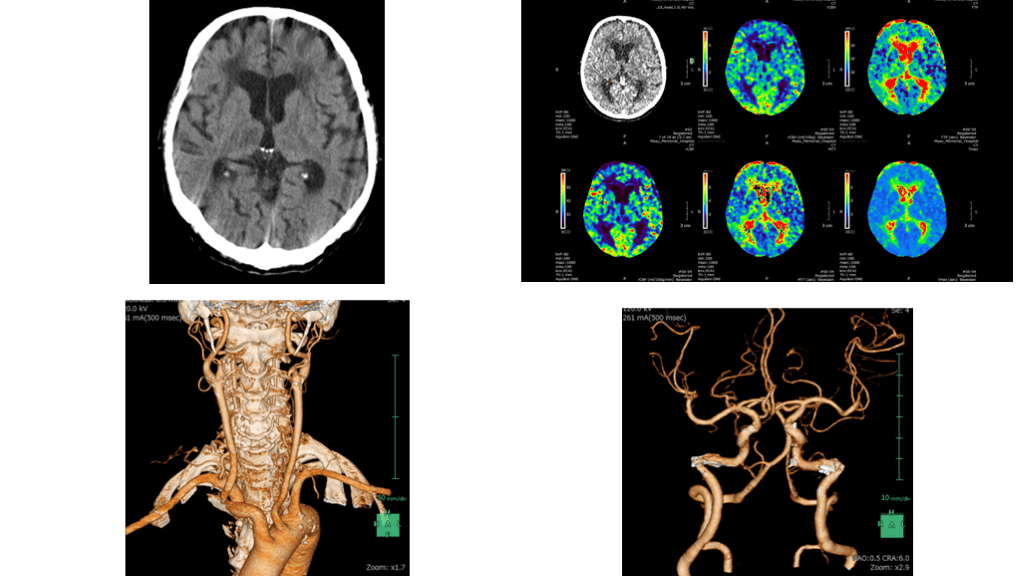

脳梗塞に伴う急性呼吸不全の症例

【救急症例検討会】脳梗塞にAKI, 急性呼吸不全を併発した症例

症例提示 90歳代男性 【現病歴】某年X月Y日午後7時頃最終健常確認。Y+1日午前8時頃、家族によって ベッド脇に座り込んで, 呂律障害・左片麻痺を来しているところを発見され救急 要請された。救急隊現着時に左片麻痺と構音障害を認めた。9時頃当院へ収容 された。 内服:近医からシロスタゾール 50mg 2T2x, ニザチジンcap150mg 2C2x, メマンチン20mg 1T1x etc. 既往歴:今年2月の頭部CT所見を基にラクナ梗塞と診断, 高血圧, 胃潰瘍, 認知症 【来院時現症】HR 127, BP 168/107, JCS I-2(GCS E4V4M6):見当識障害あり, 瞳孔径 2.5/2.5, 左片麻痺あり, 構音障害なし 【画像所見】 頭部単純CT:有意所見なし 頭部造影CT:3DCTA上は主幹動脈閉塞なし, Perfusionにて右MCA末梢再開通 を示唆する所見あり。